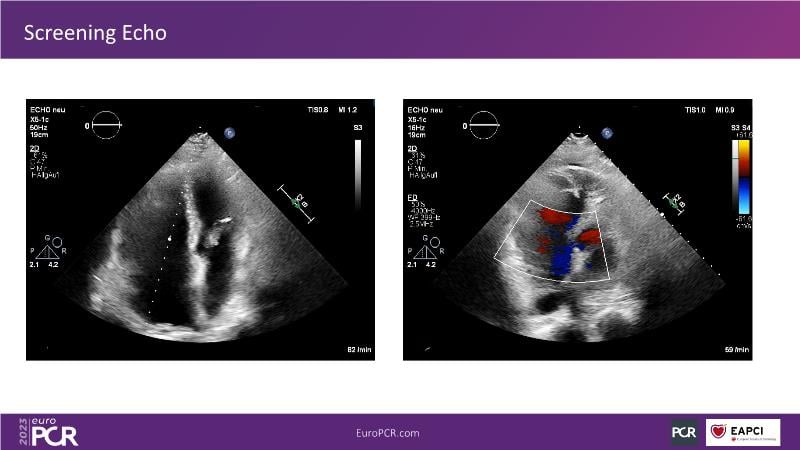

Discover the comprehensive guide to heterotopic valve replacement for patients experiencing right heart failure and tricuspid regurgitation. Join this session to gain insights into patient selection criteria, delve into the concept behind this innovative procedure, and grasp the fundamental aspects of its execution.